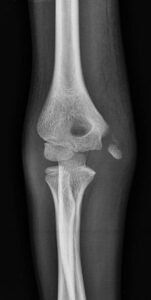

[toggle title=”Medial Epikondiler Kırıklar” state=”close”]

Çoğunlukla 10-14 yaş arası çocuklarda görülür.

Yaralanma direkt travma sonucu olabileceği gibi fleksör kas grubunun oluşturduğu avülsiyon sonucu ya da dirsek çıkığına sekonder de olabilir.

Medial epikondil kırıklarının yarısına yakınında eşlik eden dirsek çıkığı da görülür. Bu hastalarda dirsek redükte edildiğinde medial epikondil kırığı da redükte olur.

Kırık parçanın eklem içinde kalması nedeniyle redüksiyon yapılamayan durumlarda ya da kırığa eşlik eden ulnar sinir yaralanması varlığında cerrahi tedavi gerekir.